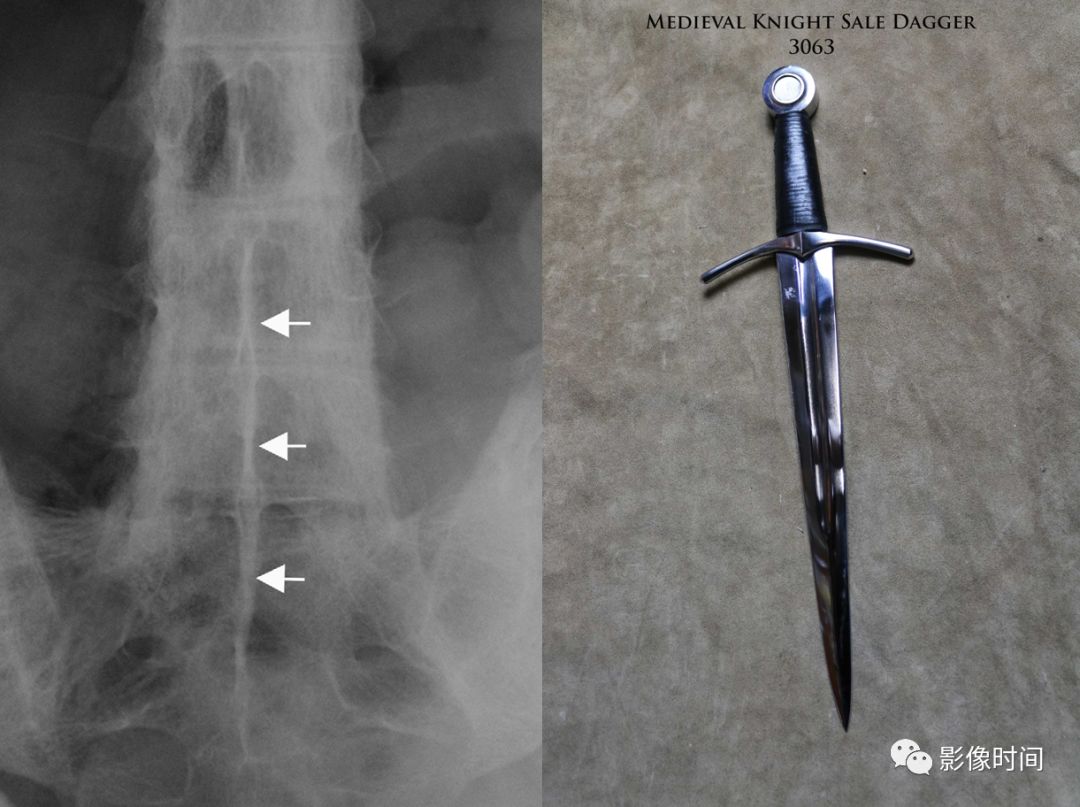

20匕首征

匕首征,或译为短剑征(Dagger sign)

匕首征是指由于棘间韧带骨化,导致在正位 X 线片上呈现垂直的一条硬化带(白箭),形似一把短而窄的匕首而得名。此征象也主要用于描述强直性脊柱炎。

典型病例

强直性脊柱炎。正位 X 线片示棘间及棘上韧带骨化形成匕首征(黄箭)。另可见双侧骶髂关节骨性融合,双髋关节间隙均匀性狭窄。